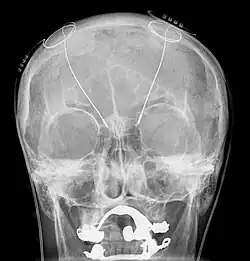

Basically it involves the implantation of electrodes into the brain. Usually they are positioned in the subthalamic nucleus but sometimes other targets can be used including the internal segment of the globus pallidus and the thalamus. Small electrical pulses are applied through these electrodes by means of a controller implanted under the skin of the chest or abdomen.